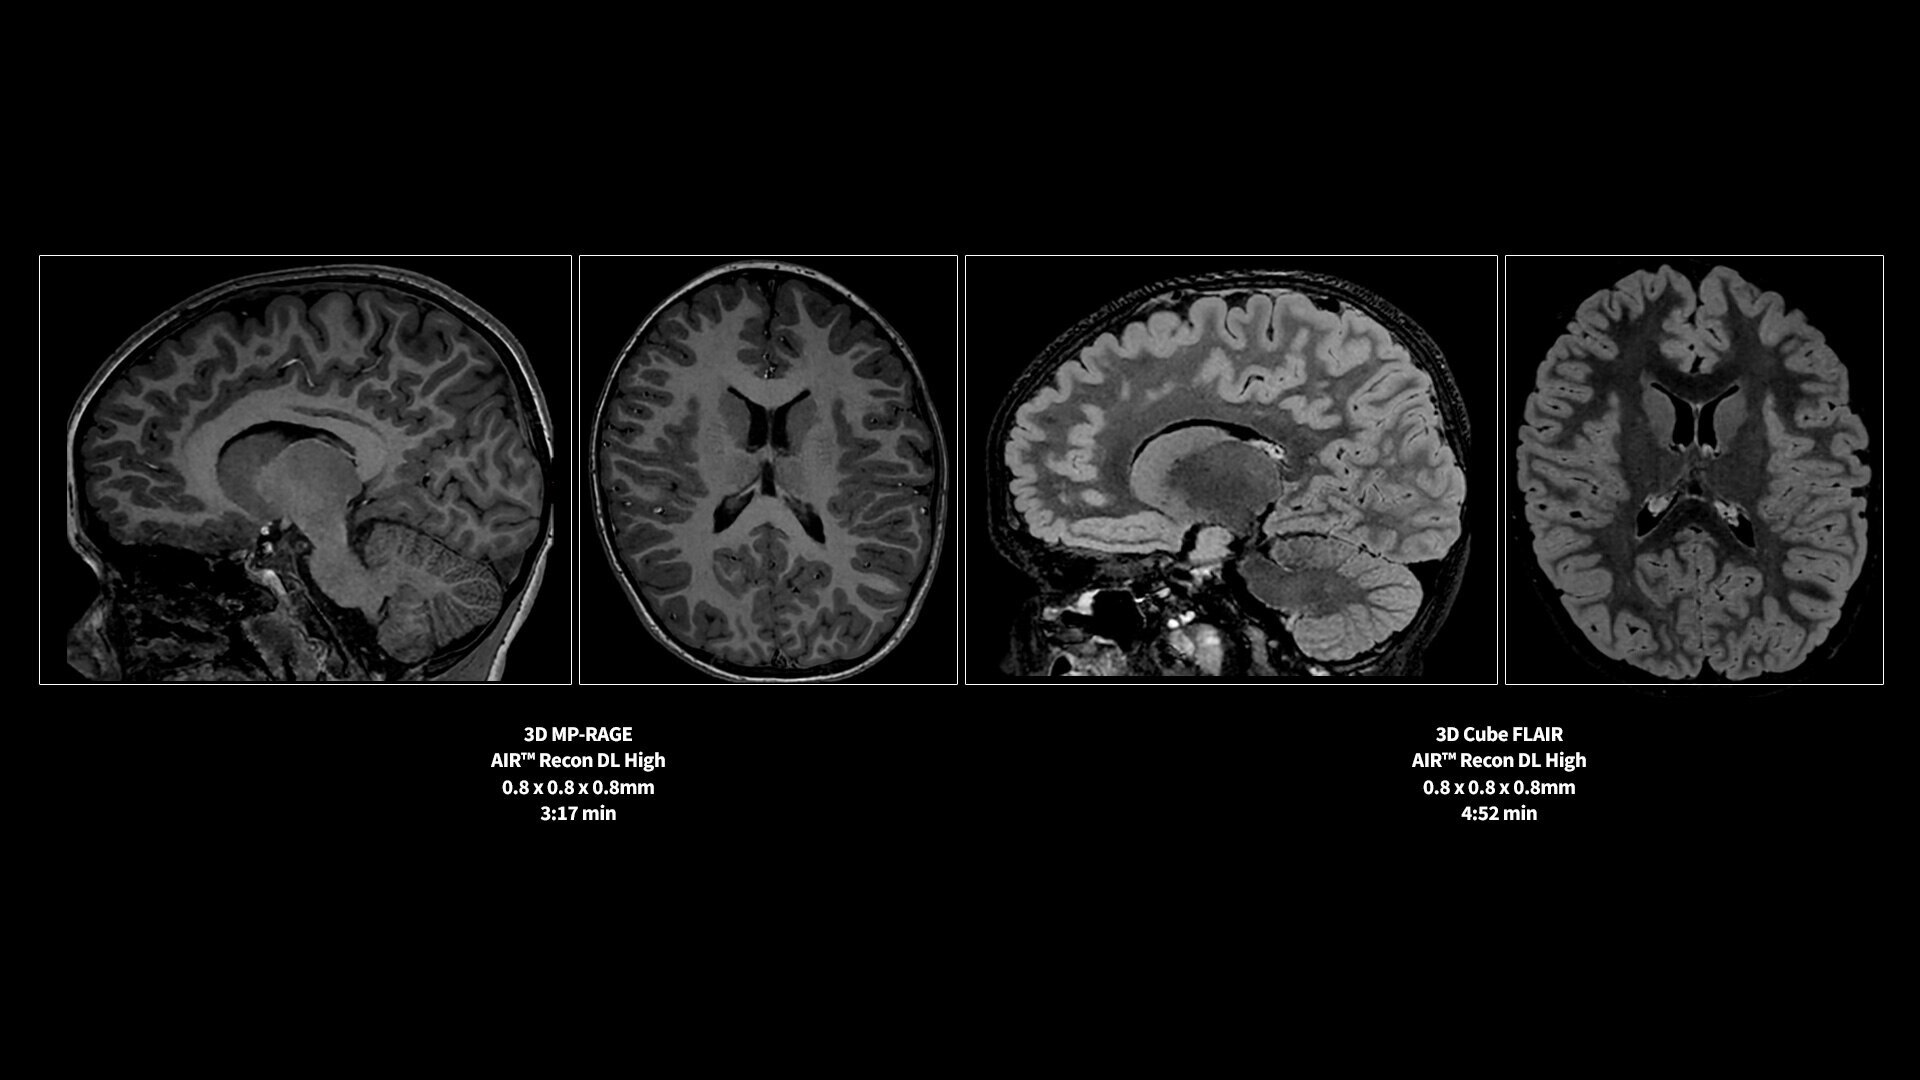

MR image reconstruction with AIR Recon DL

Evolve your MRI scanner's capabilities: experience exceptional image quality without compromising scan time.